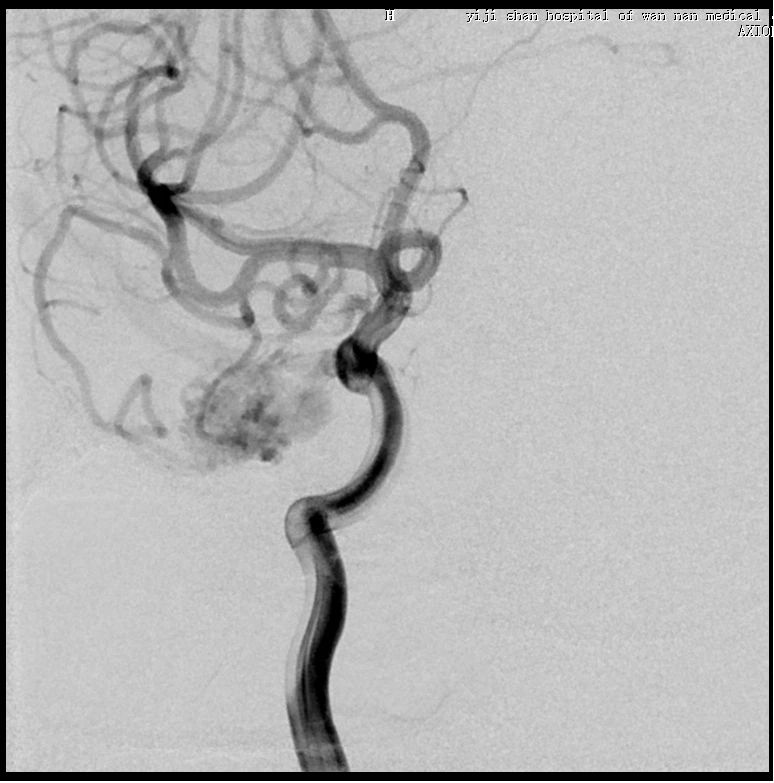

入院后脑血管造影检查提示:右侧颞叶动静脉畸形,由右侧大脑中动脉两分支血管参与供血,右侧大脑后动脉一分支血管参与供血,畸形团大小约1.1*1.3cm,通过侧裂静脉经皮层静脉引流入上矢状窦前部;并可见右侧大脑后动脉供血畸形团的分支血管血流相关性动脉瘤两枚。

1. 通过椎动脉先将Echelon 10微导管在导丝导引下超选至远端动脉瘤,填塞弹簧圈(Cosmos 4mm/12cm,Jasper 3.5mm/10cm,Axium 3mm/8cm,Jasper 2.5mm/8cm),然后逐渐回撤微导管至近端动脉瘤填塞(Axium Prime 4mm/12cm),最后可见向畸形团供血明显减弱,远端动脉瘤不显影,近端动脉瘤仍有显影。